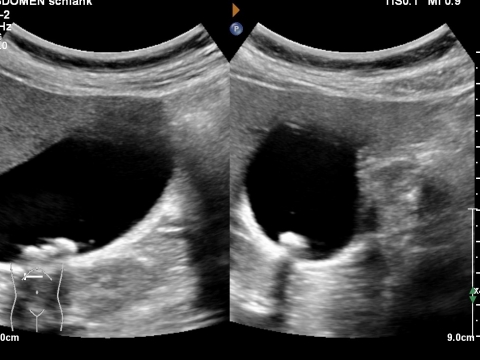

Ultraschall_Gallensteine_Praxis_Dr_Deiters